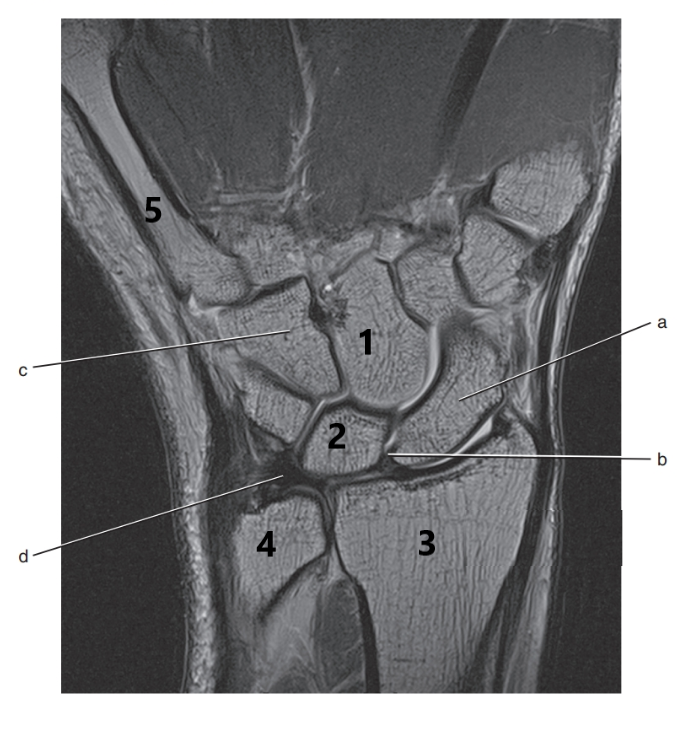

What is # 3 ?

Radius

What is letter a ?

Scaphoid

What is # 2 ?

Lunate

Triangular fibrocartilage complex

What is # 4 ?

Ulna